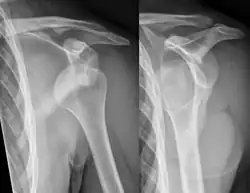

Anterior dislocation of the right shoulder. AP X ray -

Anterior dislocation of the right shoulder. Y view X ray.